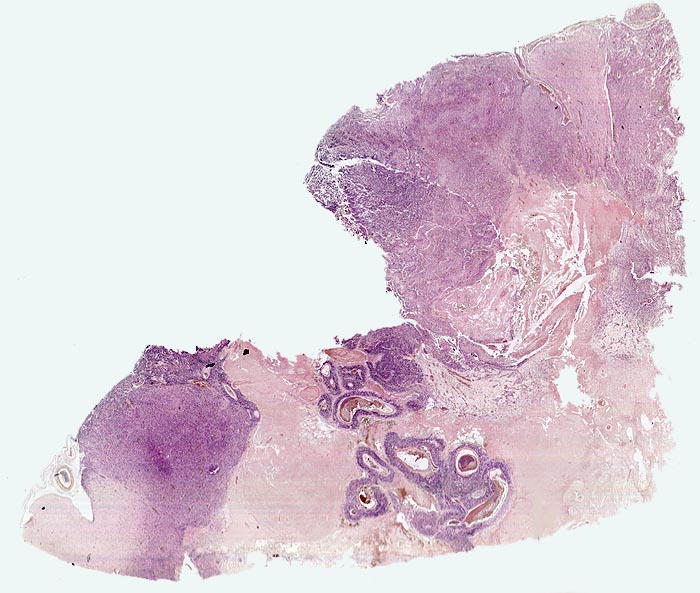

• Zellreicher Tumor mit sehr unscharfer Begrenzung zum normalen Hirnparenchym (rechts unten).

• Typische streifenförmige Nekrosen mit randständiger Palisadierung der Tumorzellen.

• Im Zentrum der Nekrose thrombosierte Gefässe umgeben von einem Saum vitaler Tumorzellen.

• Pathologische glomerulumartige zellreiche Gefässknäuel.

• Ausgeprägte Zellpolymorphie und Atypie.

• Mitosen.